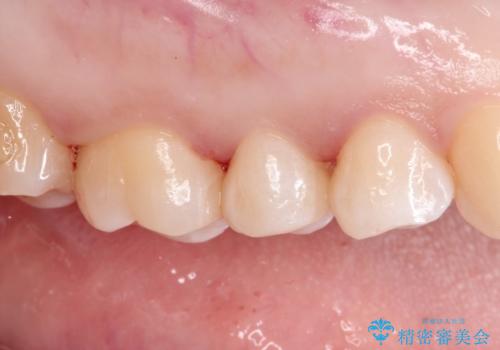

【セラミックインレー】虫歯になった詰め物部分を修復

- 前医で治療された詰め物の部分に、定期検診で虫歯が見つかったため、セラミックインレーにて修復治療を行いました。

接着時にはラバーダム防湿を行っています。